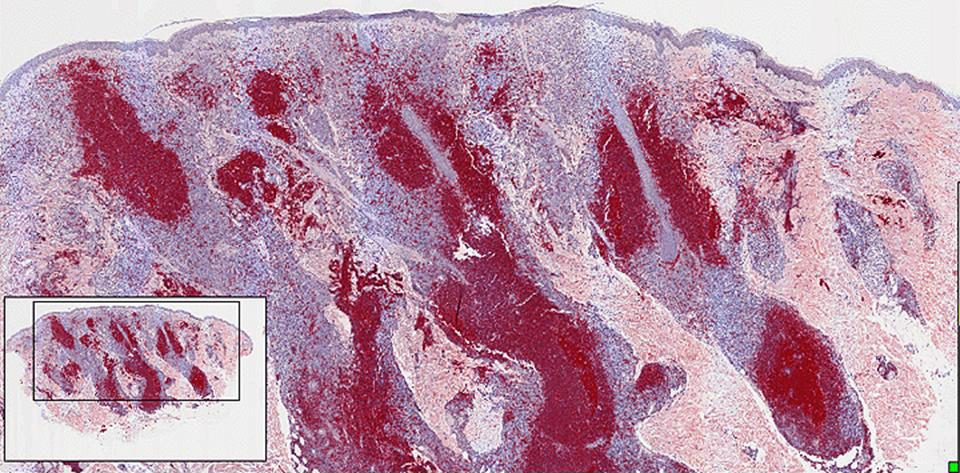

Approvato negli USA un nuovo farmaco biotech per il linfoma cutaneo a cellule T

La Food and Drug Administration americana ha approvato giorni fa un nuovo farmaco per il trattamento di un raro tumore della pelle noto come linfoma cutaneo a cellule T (CTCL), una malattia che colpisce persone per lo più di sesso maschile, di età superiore ai 50 anni.